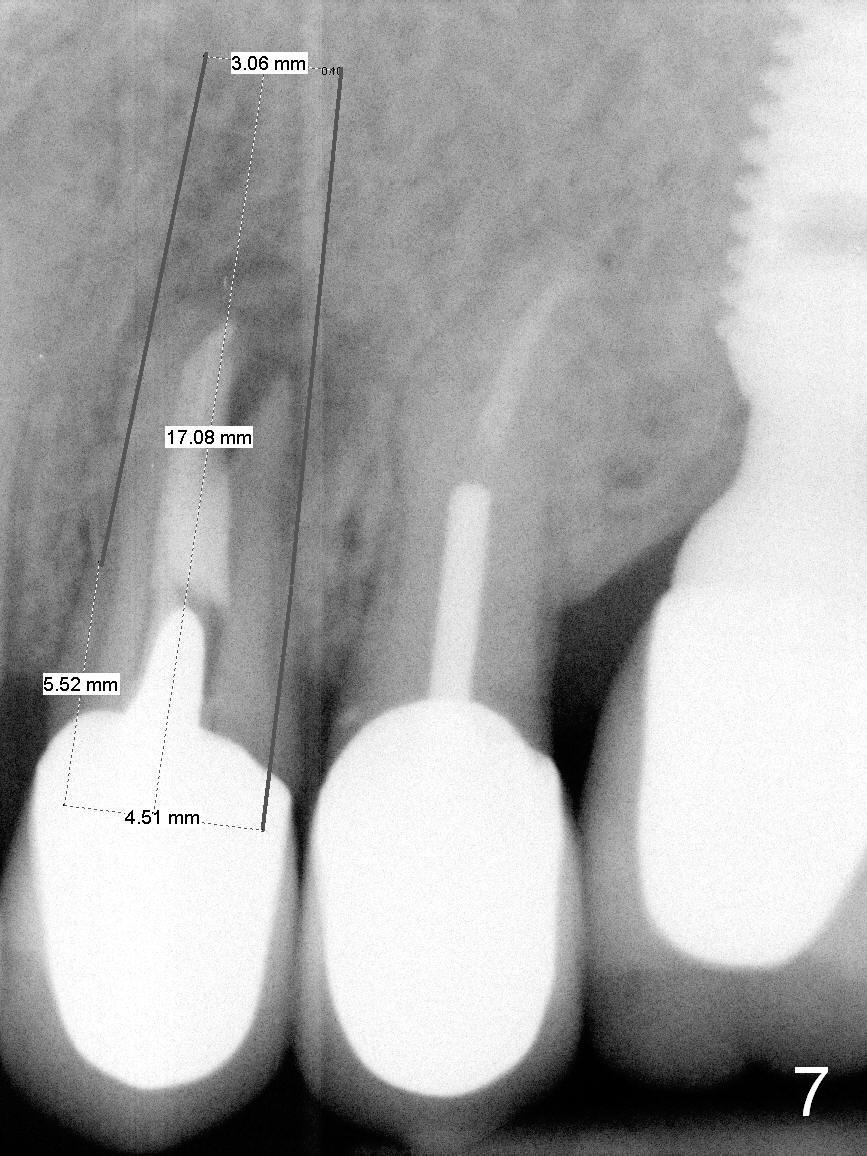

A 4.5x14 mm bone-level or 4.5x17 mm tissue-level implant appears to be appropriate for the site according to the PA (Fig.6,7).  CBCT shows that there is enough bone to place a 4.5x20 mm tissue-level implant (Fig.8).  This is more appropriate, considering the large radiolucency (Fig.5), the age of the patient (possibly osteoporosis), and the maxilla (bone softer than that of the mandible).  The implant will be supported by approximately 8 mm solid bone apically (Fig.8).

In addition, osteotomy will be under prep.  The depth of a 2 mm pilot drill, 2.5 mm and 3 mm reamers will be 20 mm, 17 mm and 14 mm, respectively.  A 4.5x20 mm tap will be inserted 17 mm before placing the corresponding implant.  Intraop PAs are to be taken following the pilot drill, tap and implant.